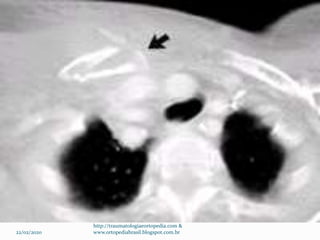

Padrões incomuns de fratura

 Separação fisária medial

 Normalmente necessário TC

 Maioria tem indicação de tto conservador

 Cirurgia: Lesão vascular ou laríngea aguda por desvio

posterior